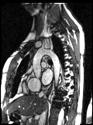

Recently FDA-approved 7 Tesla (T) MRI can provide improved signal-to-noise ratio, resolution, and image contrast when compared with standard clinical MRI scanners (usually 1.5T or 3T). However, proton imaging at higher frequencies (~300MHz) and shorter wavelength (~13cm in brain tissues) can lead to inhomogeneities in the images and potentially cause high localized radiofrequency (RF) power deposition in the tissue. The Tic-Tac-Toe (TTT) RF coil system provides improved homogeneity and reduced power deposition. It is achieved thanks to an innovative coil design and a methodology of operation. Several clinical MRI sequences have been performed and compared with commercial RF coils, demonstrating the superior performance of the Tic-Tac-Toe RF coil system. Numerous clinical studies including NIH funded studies (~2,000 subjects) are currently being conducted using this coil at the University of Pittsburgh.

b) a) c) The Tic-Tac-Toe (TTT) radiofrequency head coil for 7T MRI Fig 1: in a), the implemented 16-channel TTT transmit RF coil; in b), the computational RF coil in c), the implemented RF coil with an 32-channel receive insert Fig. 2: The B1+ (magnetic field responsible for spin excitation) field homogeneity is highly degraded at 7T MRI due to a higher operational frequency (~297MHz). The TTT presents a more homogeneous field distribution when compared with the NOVA coil (a commercial coil) [1]. Measured Tic-Tac-Toe Measured Nova coil Regions with low B Simulated Tic-Tac-Toe B + maps in the brain: TTT vs NOVA RF coils TTT coil NOVA coil TTT coil NOVA coil Image comparison with the 32-channel NOVA commercial RF coil a) b) Fig. 3: In a), Turbo spin echo (TSE) sequence using the TTT coil with resolution of 0.4x0.4x2mm. In b), the same TSE sequence acquired with the commercial NOVA coil. In c), FLAIR sequence acquired with TTT coil with resolution of 0.7x0.7x2mm. In d), the same FLAIR sequence acquired with NOVA coil. The arrows point to regions of dark spots in the NOVA coil images and compare with similar regions on the TTT coil images [1]. c) d) High-resolution susceptibility weighted images showing cortical microvessels Fig 4 SWI images acquired at 0 2x0 2x1 5mm resolution In a) an axial slice of the whole brain image acquisition In b) and c), zoomed versions of a), detailing the micro-structures a) b) c) High resolution angiography without contrast agents 380μm a) b) Fig 5: Maximum intensity projection orientation and small vessels detectability isotropic image showing whole brain isotropic acquisition In d), 0 20mm are only detectable at higher resolution

Finger tapping task: activation of Functional MRI a) Diffusion MRI and fiber tracking Post-mortem a) a) b) Fig 7 In a), an structural MPRAGE image acquired at 0 75mm isotropic (skull removed using FSL package) In b), fiber tracking based on DTI acquisition, 64 directions, 1 5mm isotropic resolution The colors are defined for different orientations of the fibers Fig 8: In a), susceptibility weighted images acquired at 0 35mm isotropic, 32 min acquisition time, in a post-mortem brain fixated with formalin In b), a photograph of similar slice in the same brain Table 1: 7T MRI studies conducted at the RF Research Facility at University of Pittsburgh White matter legions (circle): Multiple Sclerosis study Stroke (circle): sickle cell disease study Automatic hippocampus segmentation: Midlife Neurocognitive Lacunar infarct (arrow): depression study White matter hyperintensities (arrows): Healthy Brain aging study (left) and Small Vessels disease in preclinical Alzheimer’s disease study (right) Fig 9: Sample of some studies listed in Table 1 using the developed 16 array (Fig a) There are 4 completed studies and 13 ongoing patient studies with approximated 2 000 patients scheduled FUTURE DIRECTIONS 64-channel Tic-Tac-Toe RF transmit coil for 7T MRI 0 Fig 10: In a), the 64-channel transmit coil computational modeling [2] To improve the field of view of the projector/monitor in fMRI studies, the frontal panels can be removed, resulting in a 56-channel coil In b), one assembled side of the coil In c), simulated B1+ field distribution: for an 8kW power amplifier capabilities (default in older 7T MRI scanners) a homogeneity (measured by the coefficient of variationCV) of 15 2% is achieved in the brain For an 16 kW power amplifier (available for the recently FDA approved Siemens 7T MAGNETOM Terra), an CV of 10 6% can be achieved in the brain 16 kW power amplifier: 8 kW power amplifier: a) b) c) max